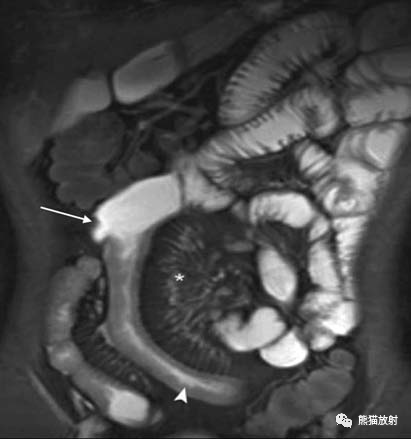

MRI显示肠系膜血管充血呈梳状征(*),小肠壁增厚(箭头)和溃疡(箭头)